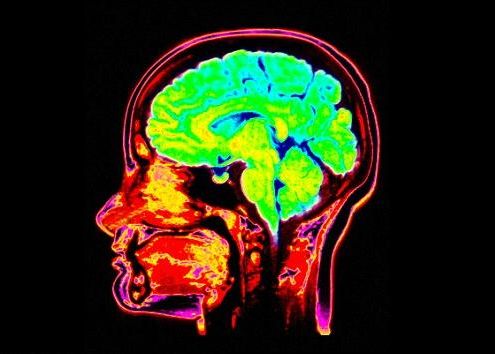

Cercetatorii de la University of California au realizat noi cercetari pe creierul uman folosinduse de RMN pentru a analiza felul in care stim sa gasim lucrurile pe care le cautam, fie ca este vorba de cheile de la masina sau telefonul mobil. Astfel, atunci cand, grabiti fiind, incercam sa gasim un lucru ratacit, parti ale creierului dedicate recunoasterii altor obiecte, ba chiar unor ganduri care n-au nicio legatura cu activitatea pe care o facem in acel moment se "activeaza" pentru a ne usura munca.

Creierul uman este mai dinamic decat se stia pana acum. 'Relocarea' resurselor sale il face sa ne ajute mai mult.

Cercetatorii au comparat partea cortexului dedicata recunoasterii oamenilor cu cea dedicata vehiculelor sau lucrurilor, rezultatul fiind foarte clar: creierul stie sa schimbe sau sa mobilizeze alte regiuni pentru ca procesul de cautare sa nu dureze mult. Acelasi studiu mai arata ca oricat de mult este solicitat cu lucruri mai importante, creierul stie sa se mobilizeze pentru o alta "misiune" aproape instantaneu.